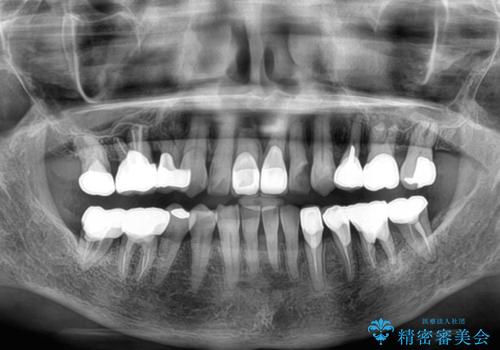

- 長年気にしていた捻れた前歯が欠けたとのことで来院された患者様です。

矯正治療に抵抗があったそうですが、前歯が欠けたことをきっかけに、矯正治療で歯列を整えた上で、セラミッククラウン治療を行う決心が付いたとのことでした。

デコボコが強いため、ブリッジや残根となっている部分のスペースを利用して歯列を整え、変色や欠けている歯をオールセラミッククラウンによる補綴治療を行うこととしました。